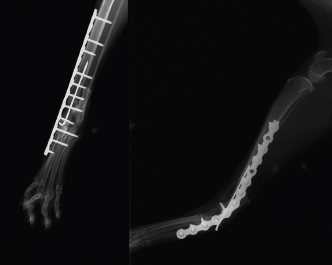

Case Details

Fig. 4. Radiographic follow-up examination 4 weeks after pantarsal arthrodesis revealing a near fusion of the arthrodesis and a fracture of the second metatarsus.